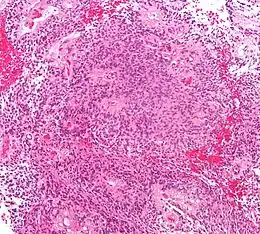

Description de cette image, également commentée ci-après

Histologie d'un épendymome. Coloration H&E.